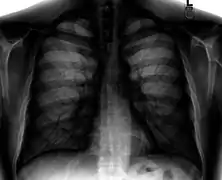

Chest X-ray PA inverted and enhanced.